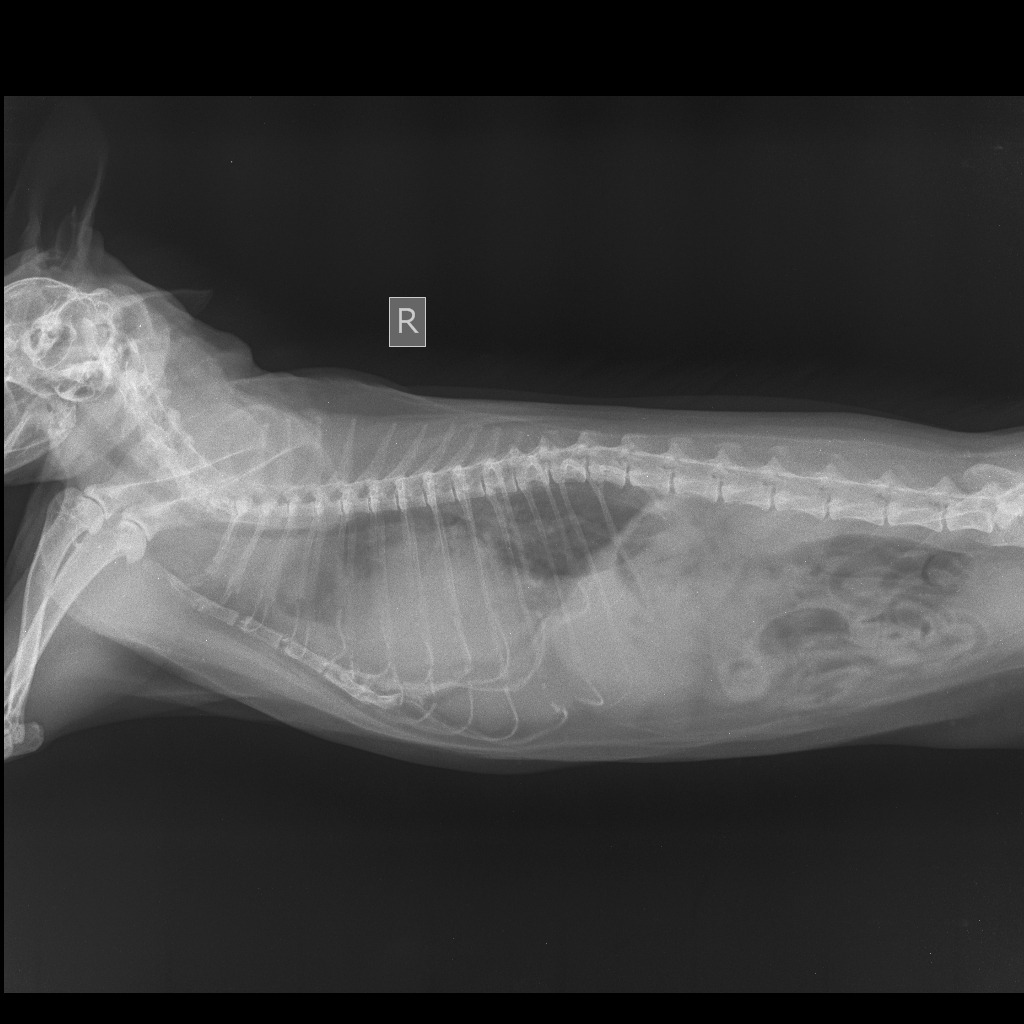

Здравствуйте!Помогите пожалуйста!! У нашей кошки 2 года проблемы со здоровьем.Частое дыхание ( с частотой 50-55 в мин),мокрый кашель и хрипы.Врачи думают что жидкость,откачивали эту жидкость 2 раза.Хотя говорят,что жидкости совсем мало,но всё равно делают пункции.Назначают мочегонные препараты.Но ей не становится лучше |

[21.07.2019 16:14] Здравствуйте! Судя по снимкам у кошки увеличено сердце.Рекомендую сделать УЗИ сердца и получить консультцию у кардиолога. |

[21.07.2019 18:03] Есть зона просветления в краниальной части. Но необходимо смотреть сам снимок(его можно увеличить), а не картинку. |

[21.07.2019 22:30] В легких воздух должен быть(более темный фон должен быть),а там наоборот. Может быть жидкость,а может быть просто фото такое. Поэтому необходимо смотреть непосредственно снимок. |